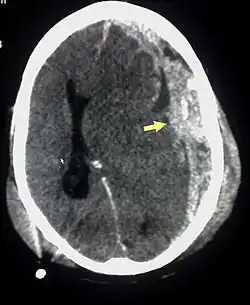

Kolikvací krevního hematomu vzniká tzv. chronický subdurální hematom. Má vlastní pouzdro a uvnitř je serózní tekutina. Vzniká nejčastěji krvácením přemosťujících žil (vedou z povrchu mozku do sinus durae matris). Téměř vždy je doprovázen mozkovou kontuzí. Chronický hematom se zvětšuje díky osmotickému mechanismu (pouzdro je semipermeabilní membránou) a díky opakovanému drobnému subdurálnímu krvácení z proliferujících kapilár na membráně hematomu. Klinicky se projevuje až s velkým zpoždění, třeba za 3 měsíce nebo za 3 roky.[2] Predisponující faktory pro vznik chronického subdurálního krvácení: starší věk, ethylismus, arachnoidální cysty, koagulopatie, antikoagulační léčba, arteriální hypertenze, epilepsie, atp.[2]

Hematom je vidět při CT vyšetření jako semilunární hyperdenzní útvar u kostí lebky (kalva).